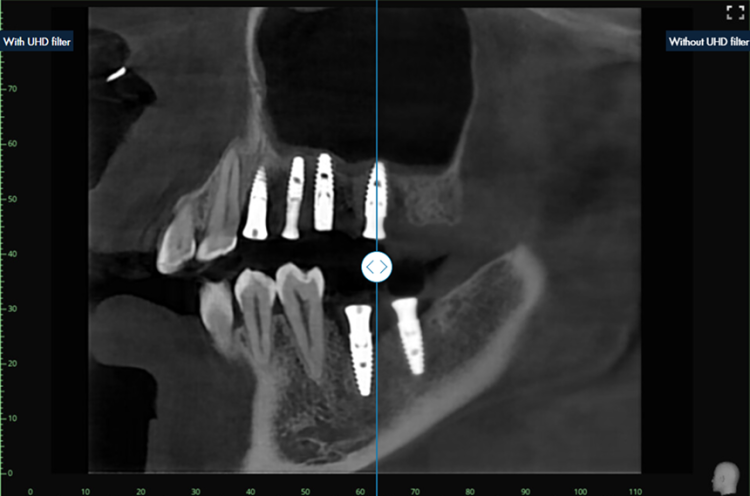

UHD Filter powered by AI

The UHD filter adjusts the brightness and contrast of the X-ray image individually and dynamically in different image areas. The result is an optimized X-ray image that enables clear and precise diagnostics. The filter is available for intraoral, panoramic, ceph and 3D/CBCT images.